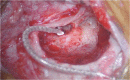

FIGURE 4

Cochlear implant electrode array after round window insertion